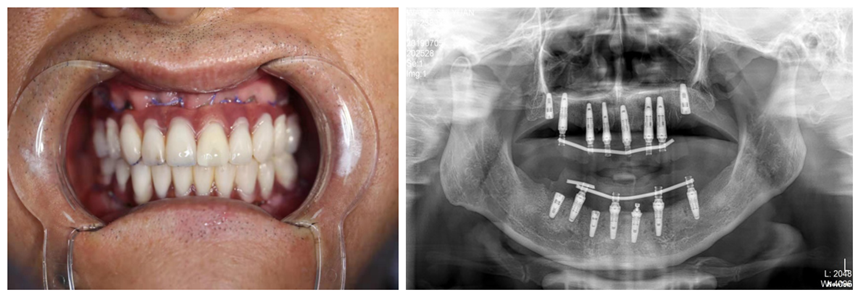

由于全口種植技術(shù)要求較高,患者王先生的骨條件又不理想,醫(yī)生在術(shù)前利用王先生的牙齒模型和CBCT數(shù)據(jù),為其制作了數(shù)字化種植手術(shù)導(dǎo)板,使手術(shù)更微創(chuàng)、更。從開始拔牙、種植到制作臨時義齒,再到后佩戴調(diào)試完畢,口腔科種植團隊整整用了12小時。當(dāng)王先生看到自己的一口新牙時,露出了滿意的笑容,開心地說:“一天的辛苦是值得的!謝謝你們,我終于有一口好牙啦!”

術(shù)后片